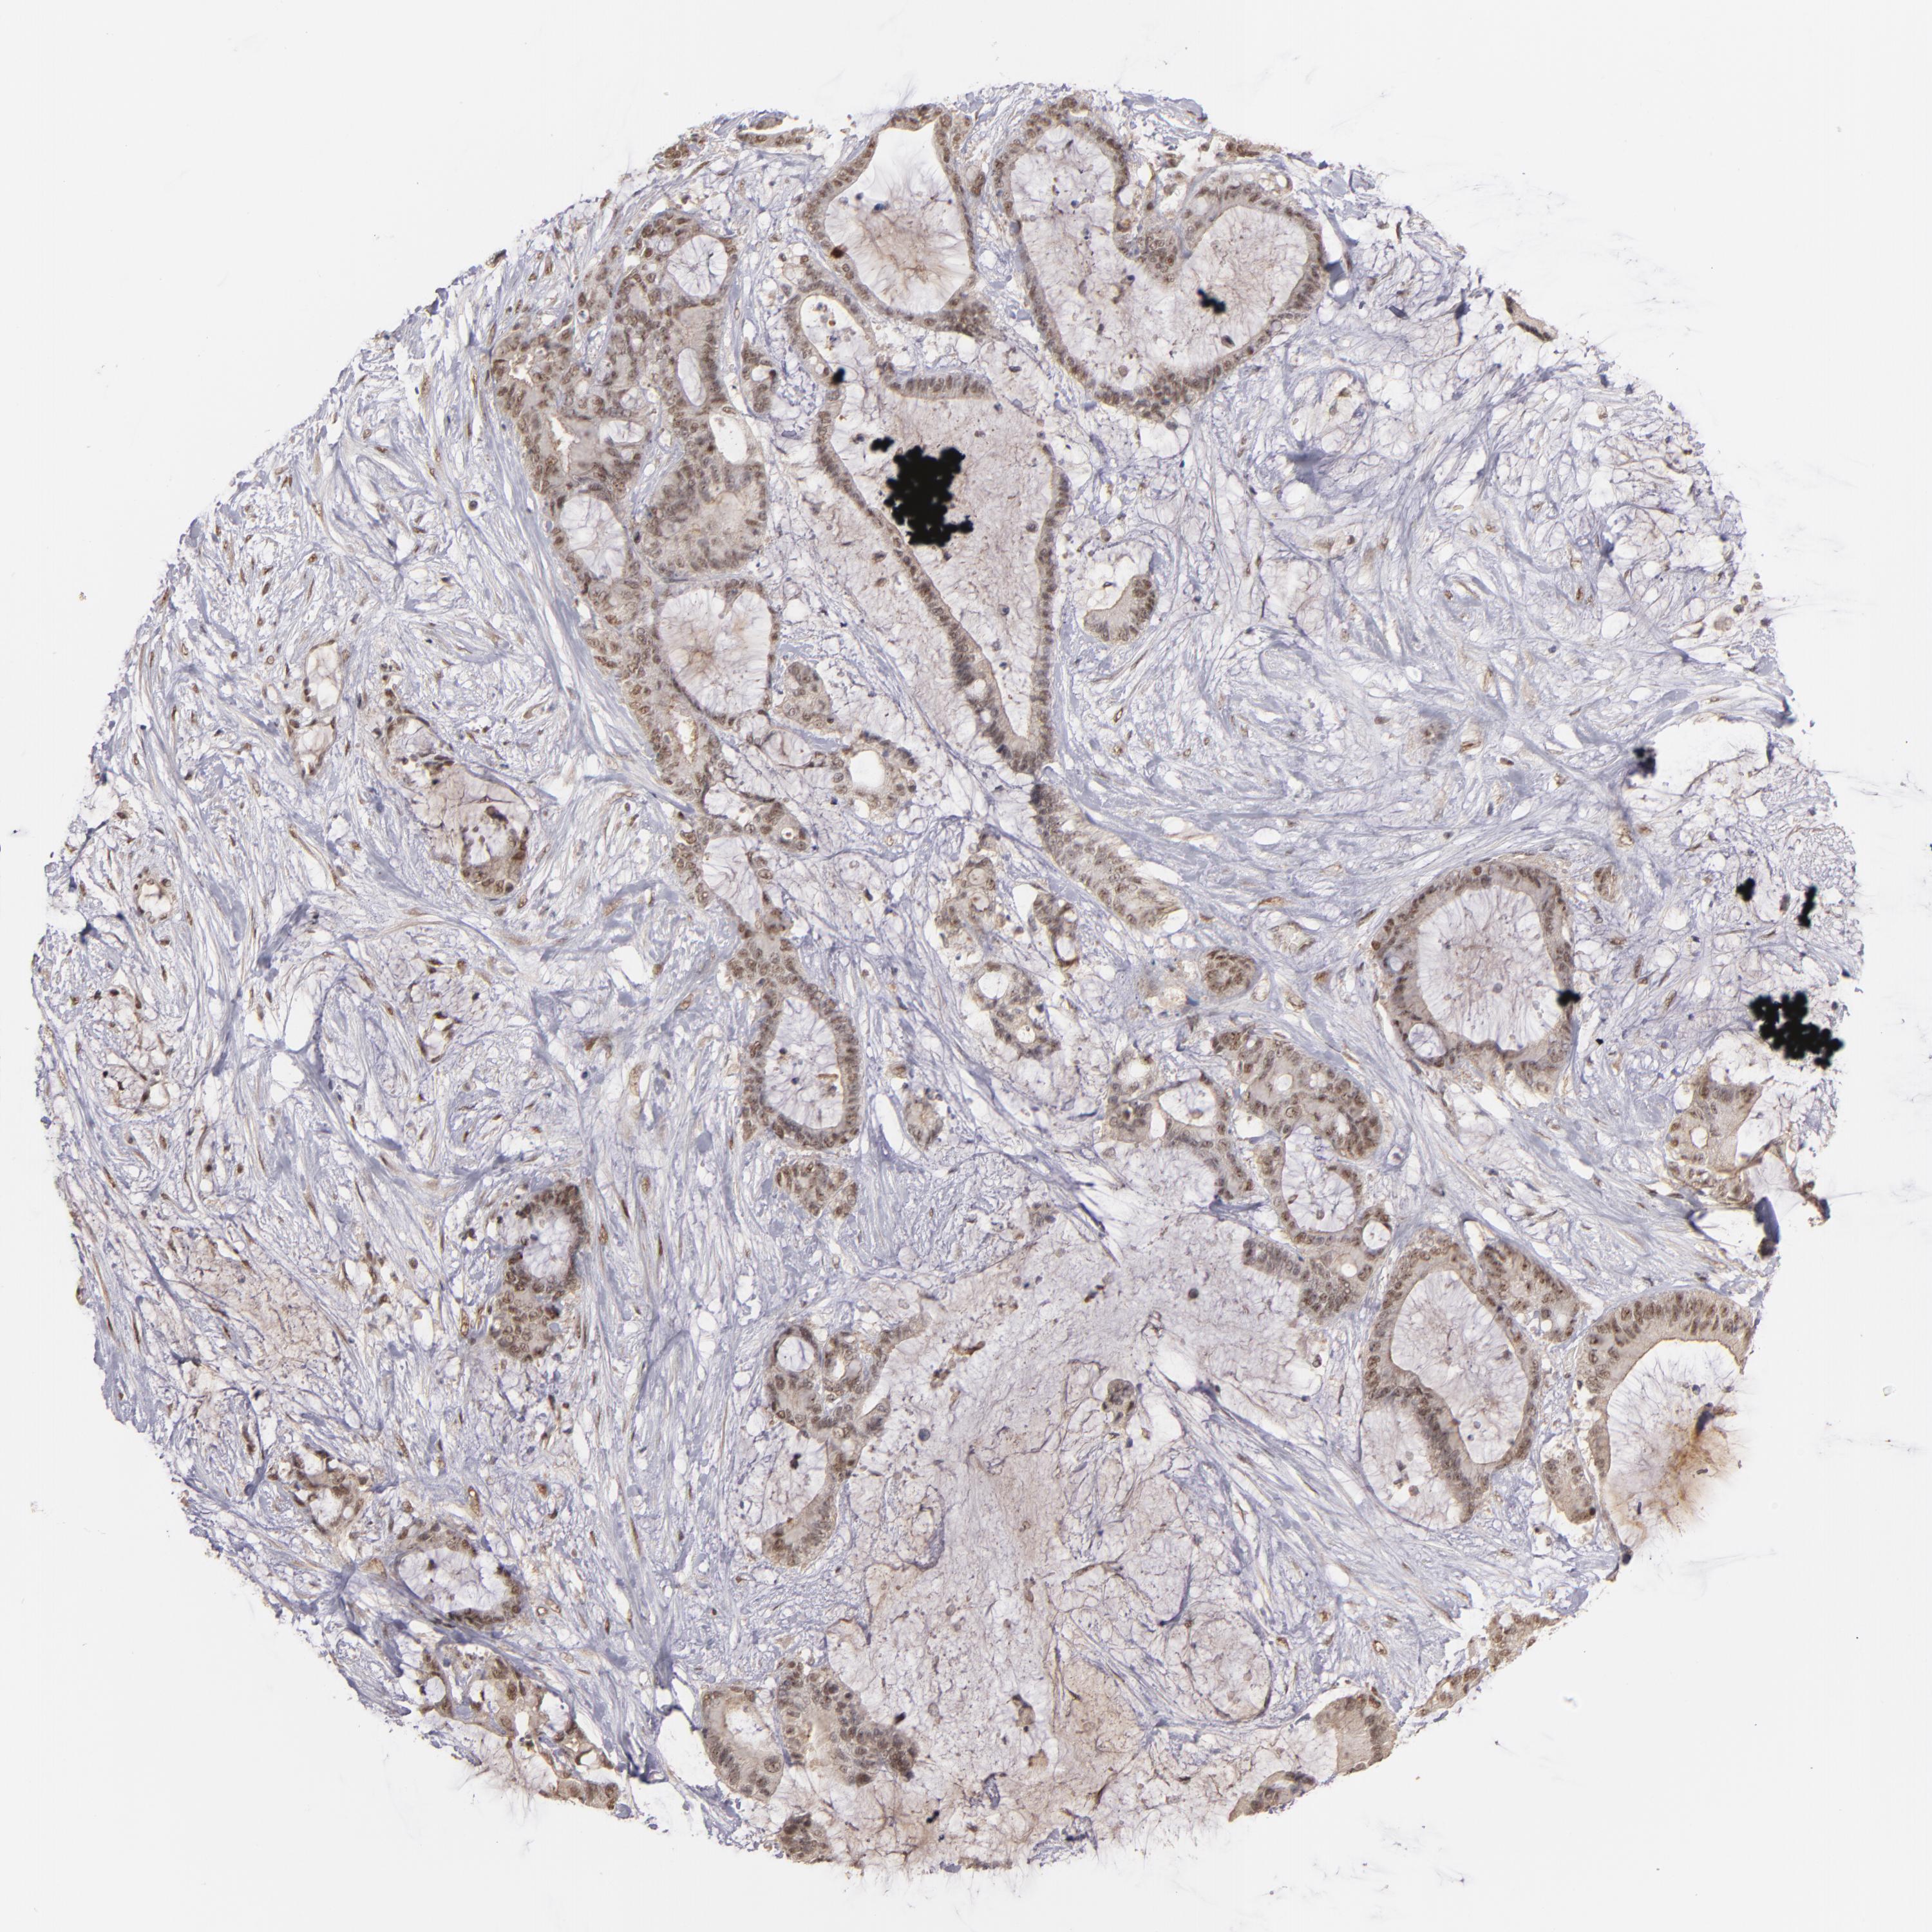

LIVER CANCER - Protein expressioni

A mouse-over function shows sample information and annotation data. Click on an image to view it in a full screen mode. Samples can be filtered based on level of antibody staining by selecting one or several of the following categories: high, medium, low and not detected. The assay and annotation is described here.

Note that samples used for immunohistochemistry by the Human Protein Atlas do not correspond to samples in the TCGA dataset.

Antibody stainingi

Antibody staining in the annotated cell types in the current human tissue is reported as not detected, low, medium, or high, based on conventional immunohistochemistry profiling in selected tissues. This score is based on the combination of the staining intensity and fraction of stained cells.

Each image is clickable and will lead to virtual microscopy that enables deeper exploration of all samples and also displays staining intensity scores, fraction scores and subcellular localization as well as patient and tissue information for each sample.

Antibody HPA001664

Staining

High

Medium

Low

Not detected

Intensity

Strong

Moderate

Weak

Negative

Quantity

>75%

75%-25%

<25%

None

Location

Nuclear

Cytoplasmic/membranous

Cytoplasmic/membranous,nuclear

Cholangiocarcinoma

Carcinoma, Hepatocellular, NOS